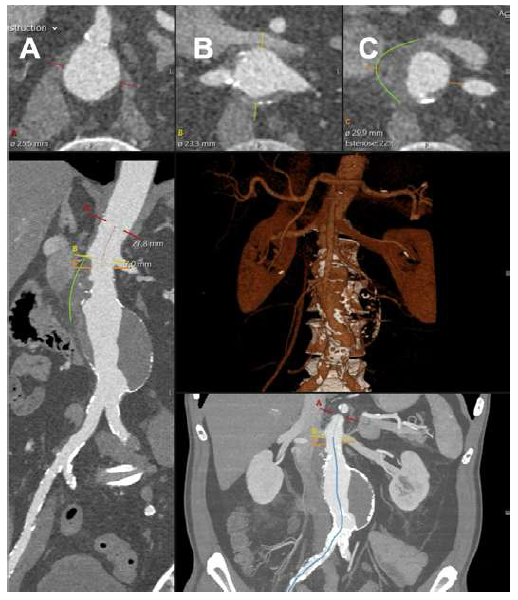

Given the patient’s sudden abdominal complaints and a previously identified AAA, a computed tomography angiography (CTA) was performed. The CTA revealed a 60 mm juxta-renal abdominal aortic aneurysm with signs of instability, characterized by parietal contour discontinuity at the proximal neck without active contrast extravasation (Figure 1).

The top panels show the superior mesenteric artery (panel A), renal arteries (panel B), and aneurysm origins (panel C). The green lines outline the signs of instability in the neck.